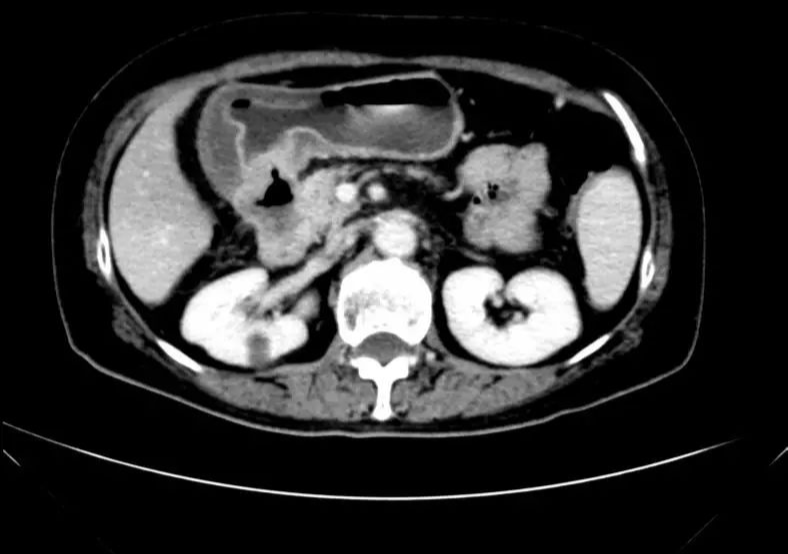

影像学表现:

• CT示:肝转移

CT-T

CT-H1

MR-H1

影像学检查结果评估:cPD。